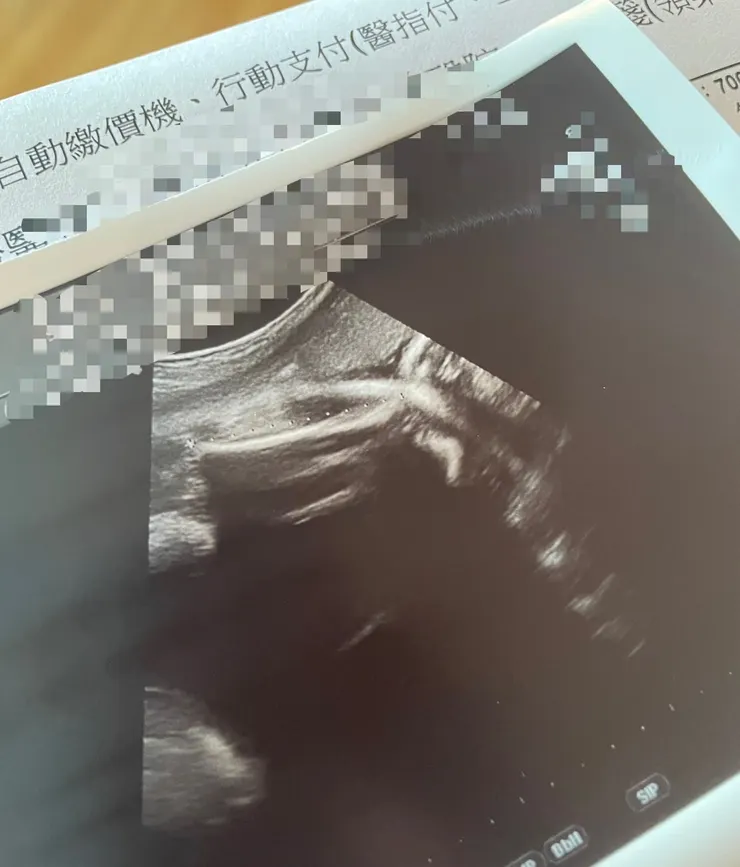

還有個趣事~是每次醫生在產檢照超音波時,從一開始到現在,寶寶都沒有正臉示人,不是背對,就是摀臉,保有很大程度的神秘感(爸爸的神秘情人),醫生給我的超音波照片,有時是側臉算是好一點,也有後頭顱、手肘(?),有次護理人員追出來,說忘了給我照片,一看.....這啥?猜猜是什麼?

竟然是大腿脛骨!?有什麼事嗎?哈哈哈哈乾脆不要給我(笑翻我了)

真的...

給我看得出東西超音波照片就好

(苦笑)